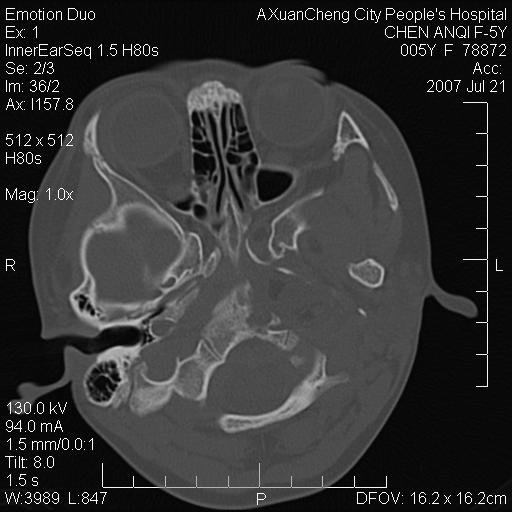

标题: PED0273:5岁,左耳流脓痛疼一周,颅底骨质破坏 [打印本页]

标题: PED0273:5岁,左耳流脓痛疼一周,颅底骨质破坏

患儿5岁,左耳流脓痛疼一周,左外耳道肉芽组织填塞 软组织窗显示病灶内结节状低密度影为气体密度

左侧中耳炎并胆脂瘤,左颞骨岩部骨质破坏并颅内感染积气。